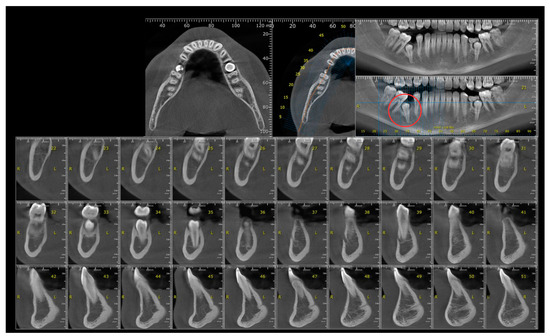

2.1. Examination, Diagnostics, and Initial Therapeutic Management